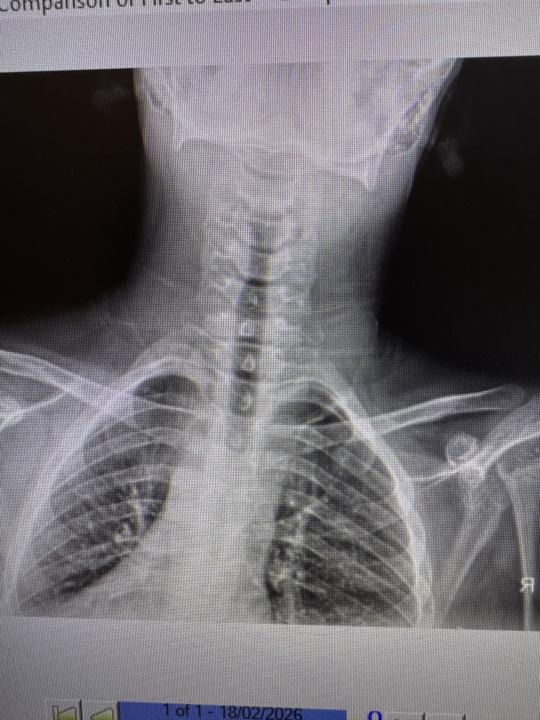

Burning sagittal suture after Ferinject infusion - into R Face/lips/ears/arms

45 y/o female who has come in with intense burning, numbness and tingling down the sagittal suture, into R temporalis, ear and lips, also into R arm and fingers. Worse in afternoon/evening. Onset 3 weeks after Ferinject infusion - initial hypophosphataemia that has since been balanced but the burning is still persisting. GP has given 75mg Lyrica to take ‘as needed’ - thoughts? Toggled L C1 today, checked & cleared spine rest of spine as per normal. I’ve got more information if needed. Some type of trigeminal neuralgia/ganglion involvement/irritation?? Other signs don’t point towards shingles… GP sent for MRI on Cx spine - Disc bulge c5-6? No report yet. I’m thinking this is more an incidental finding. What are your thoughts here? She’s back in on Monday. Further checks? Adjustments? Any labs I should consider? 🙏🏼